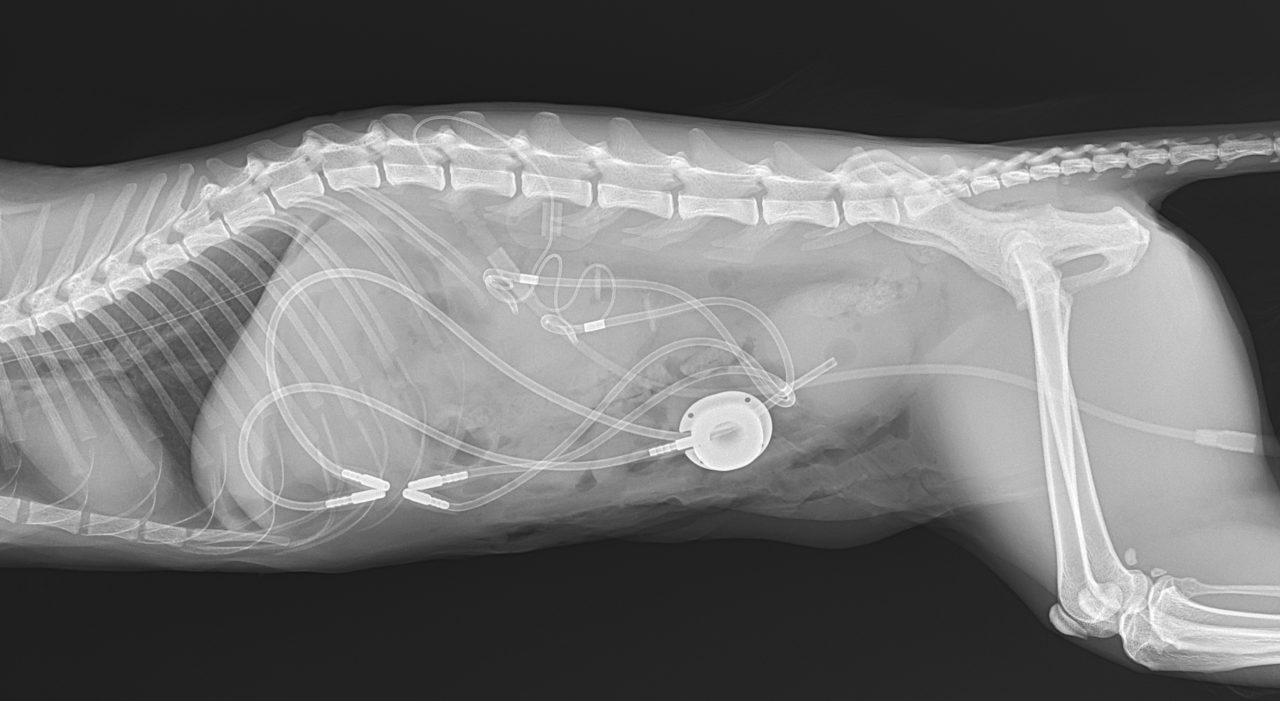

猫さんが急に具合が悪くなって、かかりつけ医を受診したところ血液検査で腎数値が著しく上昇し、高カリウム血症になっているとのこと。すぐに原因を調べて必要な処置をして欲しいとのことで来院されました。無麻酔CTでは尿管結石は確認されませんでした。すぐに拡張した腎盂に腎瘻カテーテルを設置し、尿の排泄路を確保しました。数日後アシドーシス、高カリウム血症は改善されました。尿管炎に伴う尿管の運動機能障害、エックス線に映らない結石の閉塞(99%近くシュウ酸Caなのでまず考えにくい)などが考えられましたが、腎瘻カテーテルを一時的に閉鎖すると腎数値が上昇傾向にあるため、両側の尿管の機能障害と判断しSUBシステム(人工尿管)によるサルベージを行いました。手術の翌日には腎数値は正常に回復しました。CTによる猫の尿管結石の検出感度は非常に高く、術式の決定や治療方針について細かい評価が可能です。今後は血液検査で腎数値のモニタリングを行いながら、定期的にインプラントの洗浄やメンテナンスが必要になります。